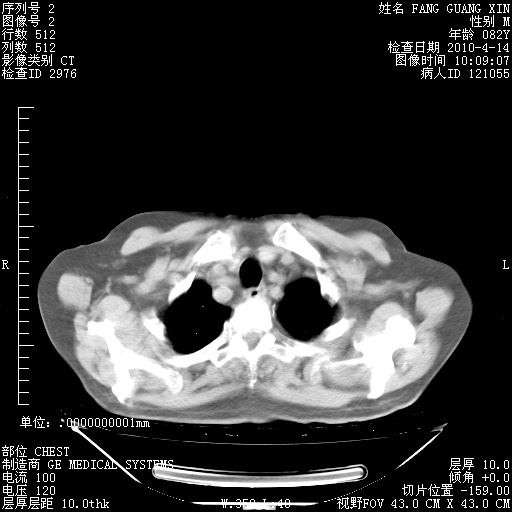

4月14日肺部CT

23.JPG

24.JPG

25.JPG

26.JPG

肺部CT平扫未见异常。